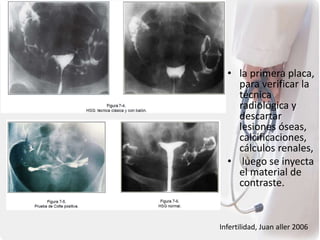

Histerosalpingografía.

• 8 y 10 del ciclo

• estudio radiológico, contraste a

traves del cervix

• Se realiza en los días que siguen

al final de la menstruación

• Terapéutico: relacionado con la

descongestión mecánica de la

trompa, la actividad

bacteriostática del contraste y la

estimulación de la actividad ciliar.

Procedimiento.

Canula se estabiliza

uso de un catéter

de plástico

con un balón cerca

de la punta.

• la primera placa,

para verificar la

técnica

radiológica y

descartar

lesiones óseas,

calcificaciones,

cálculos renales,

• luego se inyecta

el material de

contraste.

• Se toman 1 o 2 proyecciones oblicuas, derecha

o izquierda, que sirven para evaluar la versión

uterina, la anteversoflexión (AVF) o

retroversoflexión (RVF)

La placa de Cotte se toma a

los 20 minutos de haber

retirado la cánula, cuando

se usa material

hidrosoluble y a las 24-48

horas, si se utiliza medio

liposoluble

ésta permite visualizar el contraste

en la cavidad peritoneal y, por

tanto, evaluar la permeabilidad

tubárica